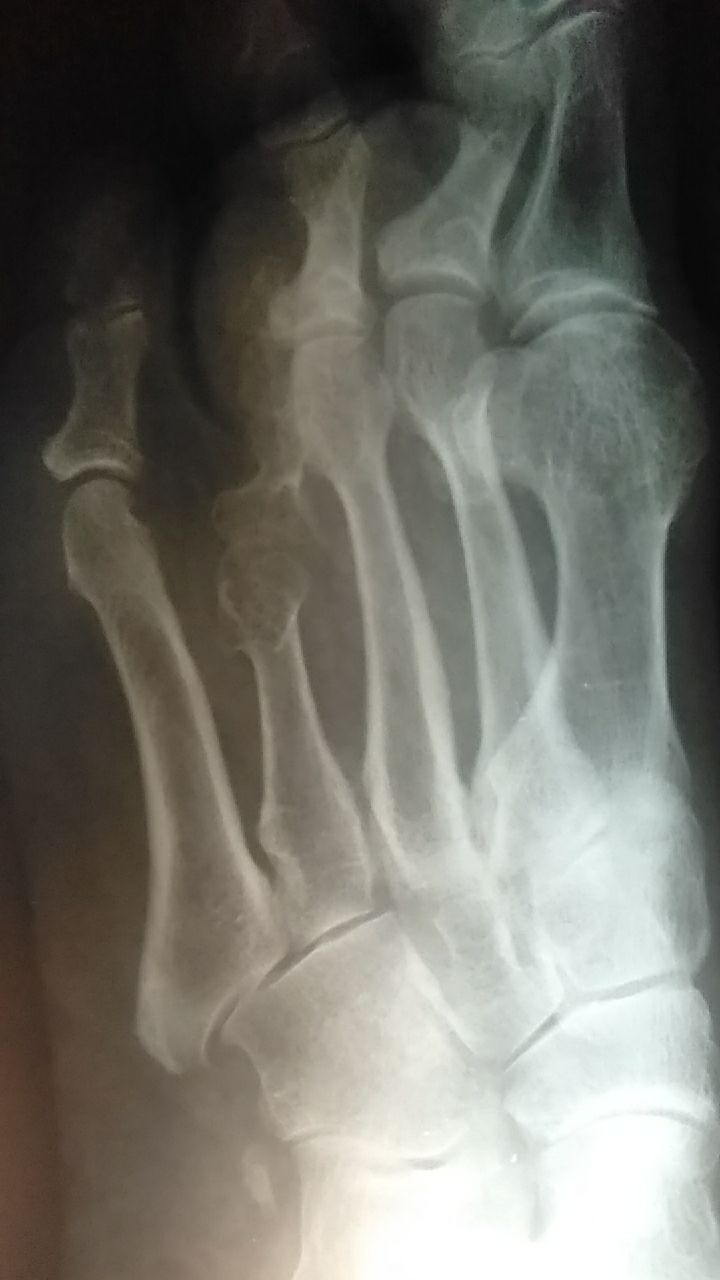

Здравствуйте, можно ваше мнение. Что это может быть. Пац. 35 лет, снимок с трав. пункта- ударился в быту, болит стопа

Брахиметатарзия